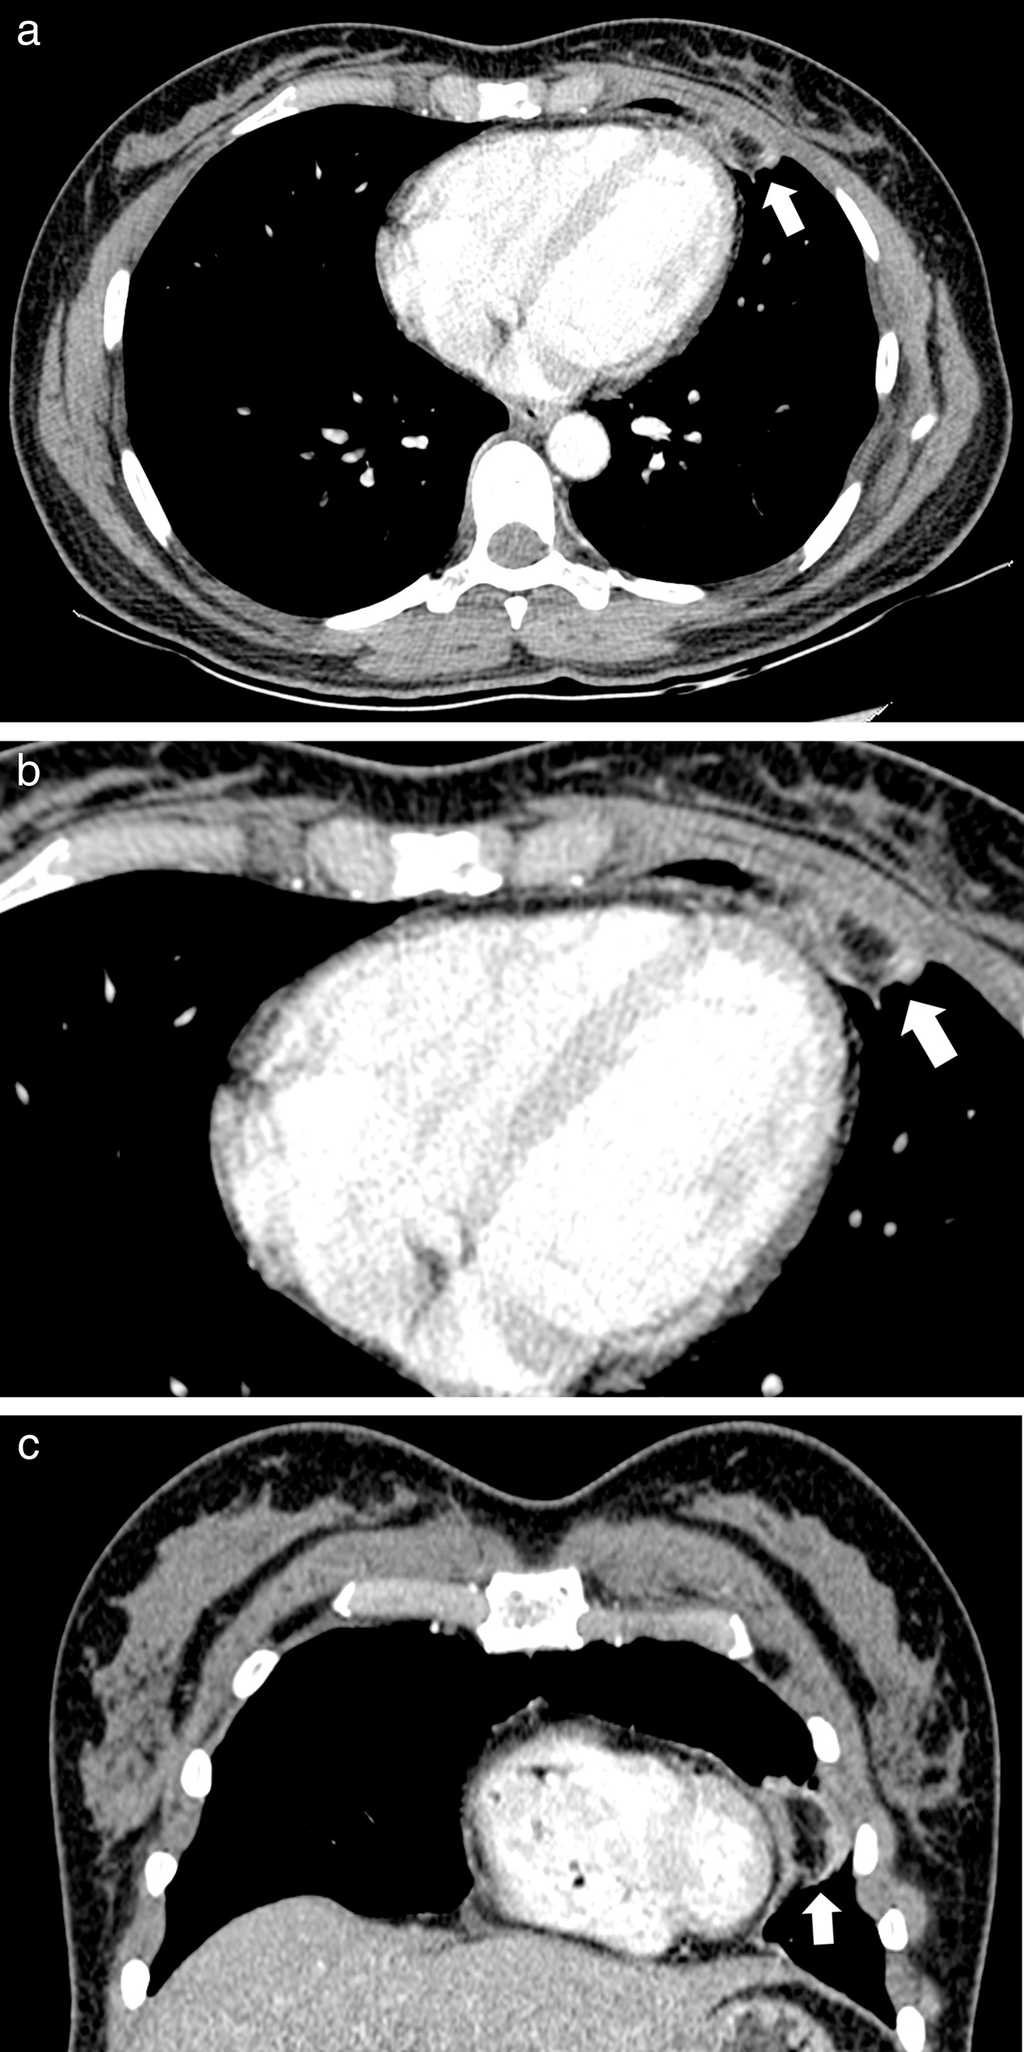

Comunicamos dos casos de necrosis grasa epic??rdica diagnosticados por TC. El primero consisti?? en una mujer de 35 a??os de edad, anteriormente sana, que consult?? al servicio de urgencias por un dolor precordial intenso y s??bito. A su ingreso el examen f??sico result?? normal, con electrocardiograma sin evidencia de alteraciones. Dada la persistencia e intensidad del dolor, se realiz?? una TC de t??rax contrastada, en la que se observ?? una lesi??n ovoidea encapsulada, con atenuaci??n grasa y presencia de anillo de tejido blando, con aumento en la atenuaci??n de la grasa adyacente, localizada en la regi??n epic??rdica anterior izquierda (fig. 1).